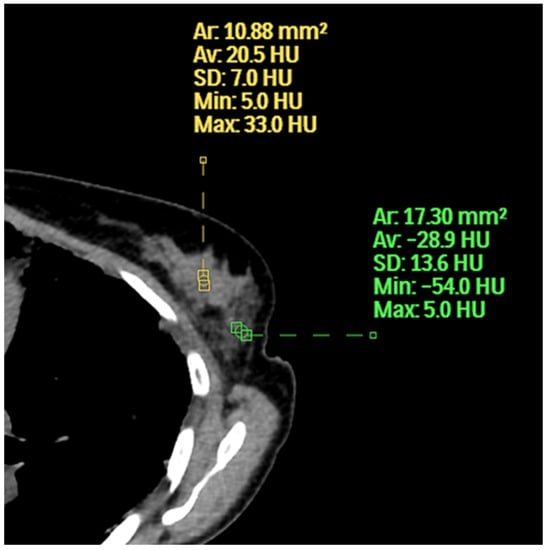

Figure 6. The inner aspect of the left breast has a higher average HU and maximum HU than the outer aspect.

For this paper, we used the term extent of fibroglandular tissue instead of breast density because, on chest CT, one can see that all hyperdense areas relative to fat are not the same. There are higher and lower areas of breast density as measured by HU (Figure 6). The HU is a measure of the absorption/attenuation coefficient of radiation on CT and the density of tissue is proportional to the measurement [15]. The average breast density on mammography was higher than chest CT because mammography underestimates the amount of fat due to overlapping soft tissue. Perhaps not surprisingly, many cancers occurred in patients with low breast density because the occurrence of cancer is increased by not only the extent of the disease but by years of exposure. This topic goes beyond the scope of our manuscript but is well described in Boyd’s calculation of the cumulative percent mammographic density which considers age [16].